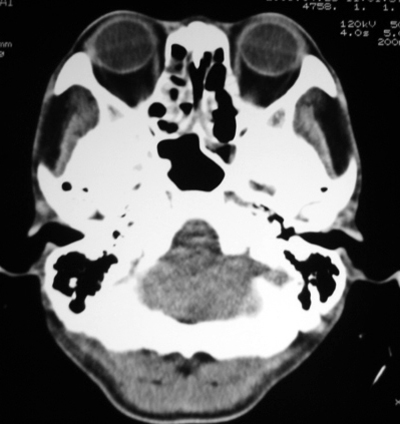

以下是引用随光逐影在2009-4-23 19:35:00的发言:[br]1)鼻咽、口咽、左侧鼻腔及右侧鼻后孔处新生物,考虑息肉可能性大。2)双侧上颌窦及双侧筛窦炎症,不排除双侧上颌窦内息肉可能。